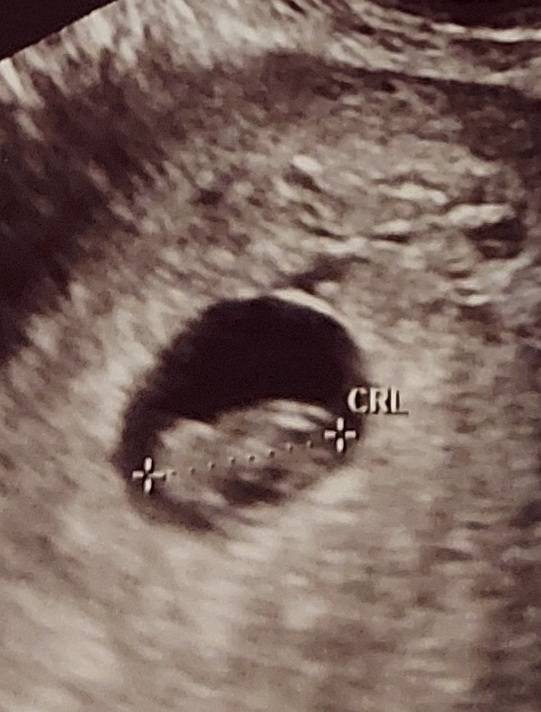

Dziewczyny gratuluje piękne widokiAle masz super zdjęcie [emoji3059][emoji3059][emoji7] U mnie kiepskie, ale też wszystko super. I termin mam na 11.11.2022. Czyli zgadza się, że beta rosła wolno bo późno wyszedł maluch. Serce też bije pięknie i nawet słyszałam[emoji3059][emoji3059]Zobacz załącznik 1384763